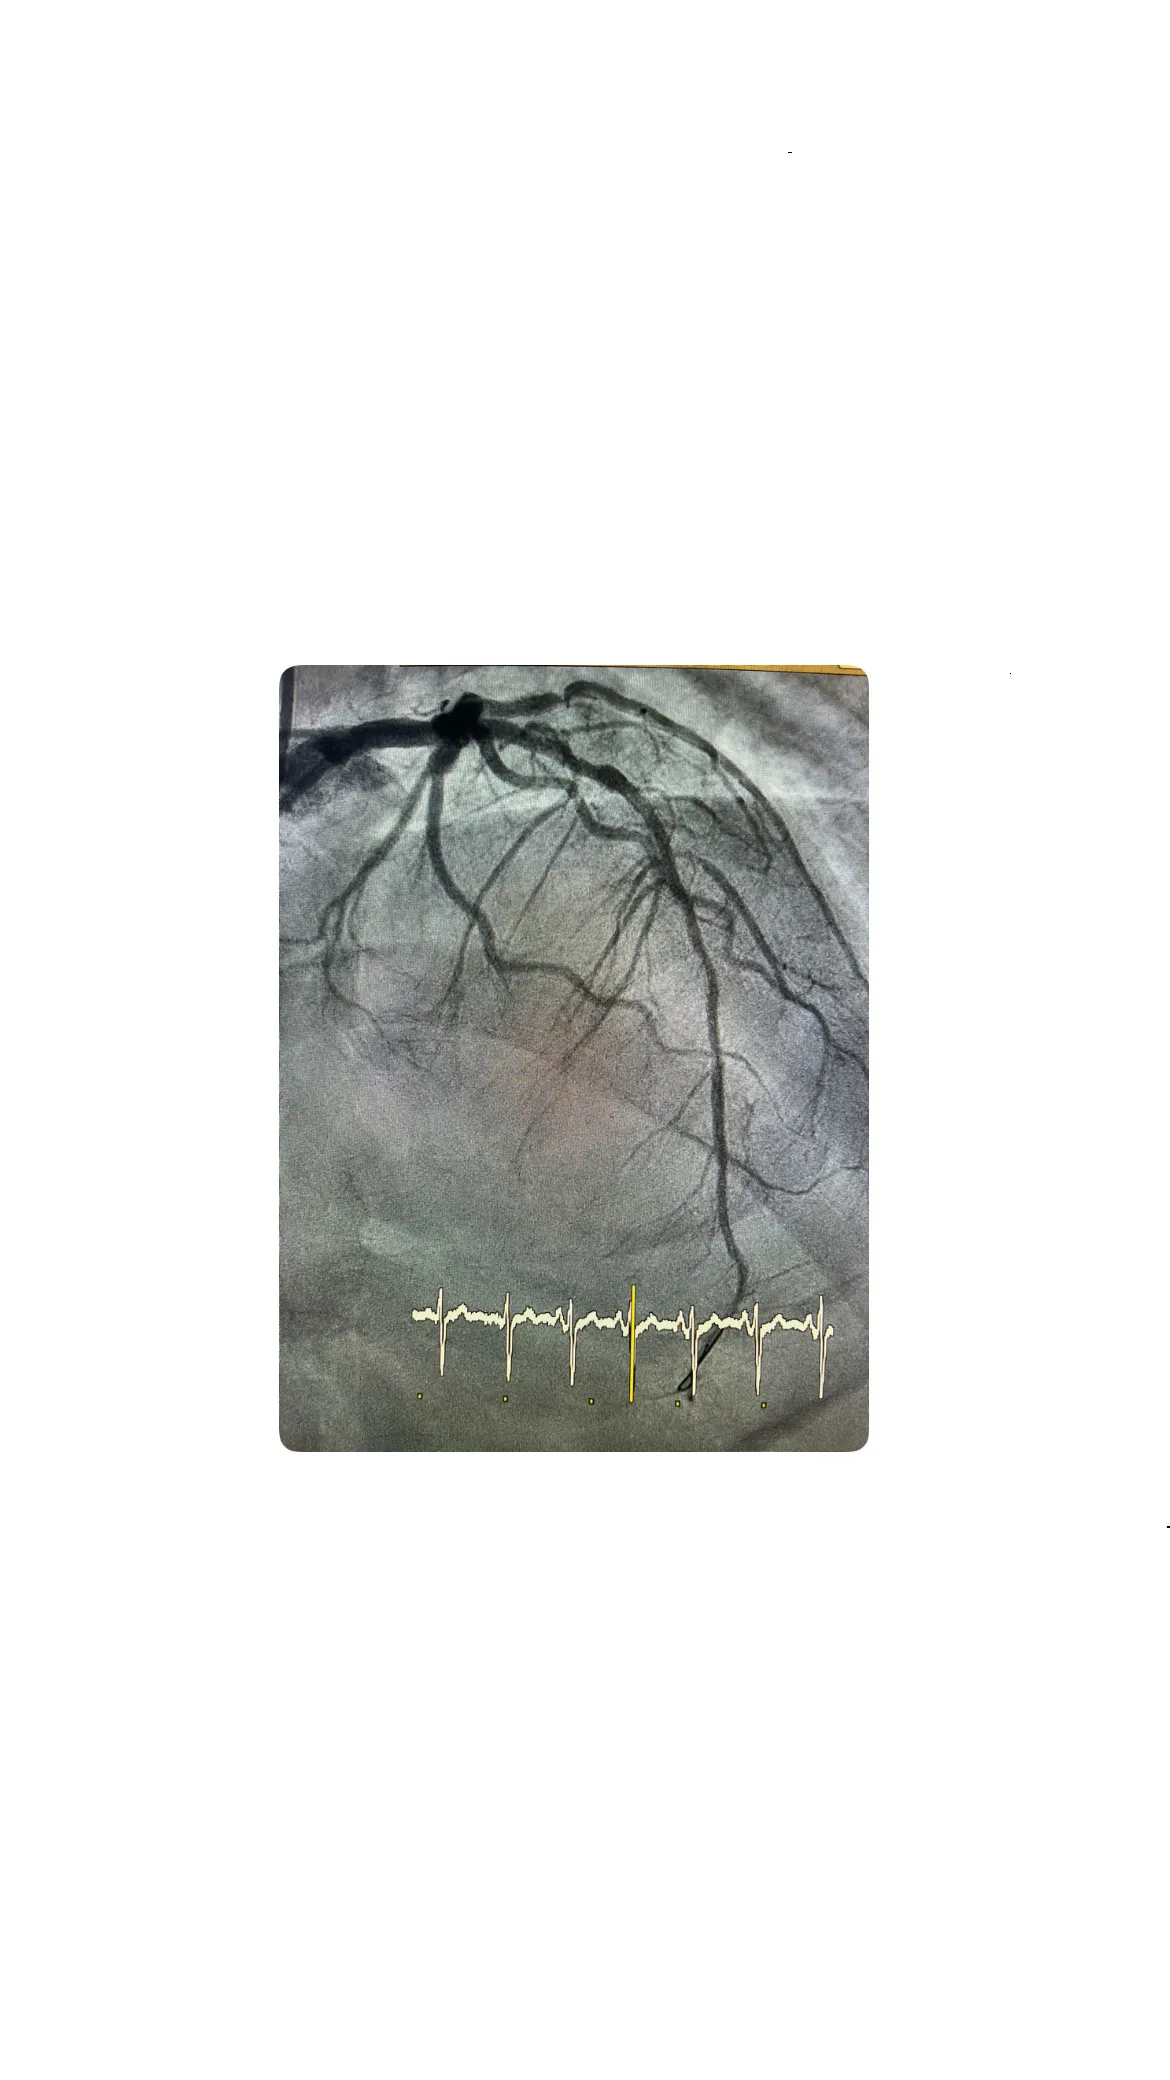

Con el acceso radial conseguido, el hemodinamista introduce una guía y comienza a avanzar el catéter hacia las arterias coronarias. En primer lugar, se comprueba la arteria coronaria derecha, ya que es importante confirmar que no está ocluida y descartar otras localizaciones de isquemia. Esta revisión inicial permite tener una visión global de la situación coronaria del paciente antes de centrarse en la arteria sospechosa. Una vez verificado que la coronaria derecha no presenta la oclusión responsable del cuadro, se decide ir directamente a tratar la coronaria izquierda, que es la que se sospecha implicada en este infarto de localización anterior.

Para ello se utiliza un catéter guía específico, diseñado para poder realizar una angioplastia de forma segura y eficaz. Al inyectar contraste en la coronaria izquierda, se observa que la arteria que falta en la imagen es la descendente anterior (DA), lo que confirma que la oclusión responsable del código infarto se localiza en este vaso crítico. La rapidez en identificar la lesión y en orientar el tratamiento hacia la descendente anterior es esencial, ya que esta arteria irriga una gran parte del ventrículo izquierdo y su reperfusión precoz marca la diferencia en el pronóstico funcional del paciente.